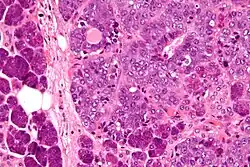

Micrograph of an epithelial-myoepithelial carcinoma (right of image). The epithelial component has a tubular morphology and is evident only focally (upper left of image). Benign serous glands (parotid salivary gland) are also seen (left of image). H&E stain.

This tumour is characterised by biphasic tubular structures composed of inner ductal and outer clear myoepithelial cells.

Its appearance is very similar to adenomyoepithelioma of the breast, which may be the same tumour at a different anatomical site.[3]